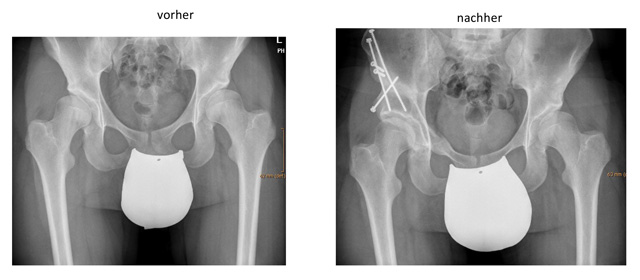

Bei der Operation wird der Beckenknochen in der Umgebung der Pfanne kontrolliert durchtrennt und die Pfanne dann neu orientiert und meist mit Schrauben wieder fixiert. Dadurch kann die Pfanne bezüglich Tiefe und Ausrichtung verändert werden.

Chiari-Ostetomie